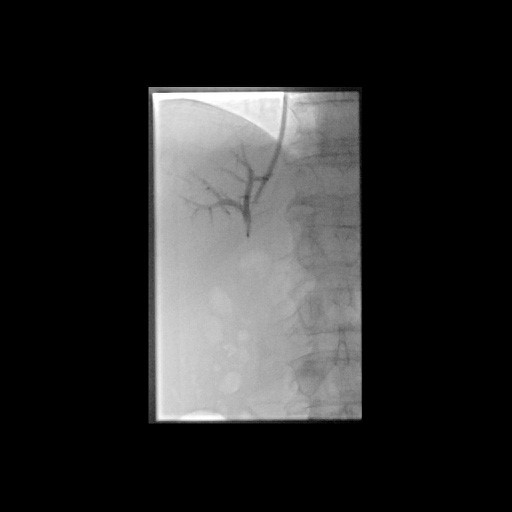

Postoperative abdominelle Blutungen bei chronischer Pankreatitis (Pfeile: Art. hepatica und Art. gastroduodenalis).

(Bild 1 von 5)